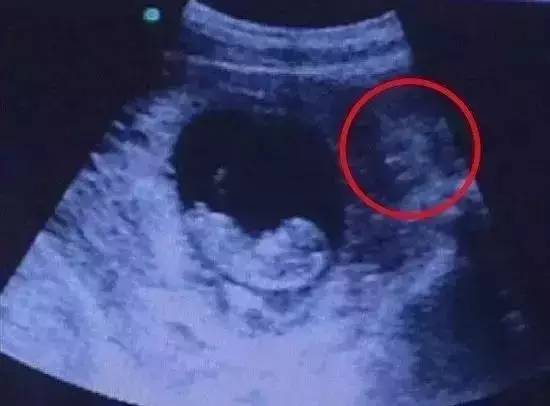

好吧,B超影像的确是出现了不少奇葩图片哦,仔细看这个红圈,这里竟然有人说是个小恶魔在看着宝宝啊!当然,也有人说是守护者,无论如何,这样的B超照片真的好神奇!